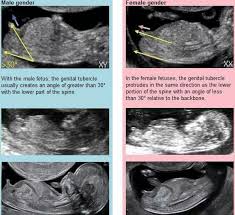

Boys and girls genitals develop along the same path with no outward sign of gender until about nine weeks. If you have an amnio at 16 weeks you can find out by 18 weeks. The gender of your baby is revealed at your second scan between 18 and 21 weeks but there s another test people use to determine if it s a boy or girl credit. It is normally possible to tell the gender from a scan after 16 weeks sometimes earlier at 12 weeks if the nub theory is used.

Ultrasounds may reveal sex organs by 14 weeks but they aren t considered fully accurate until 18 weeks. Getty contributor the nub theory. Other people have said they were told at their 12 week scan which seems optimistic to me. But of course many little babies are not accommodating and don t let the sonographer have a good enough look to see if they are a boy or a girl.

Since an ultrasound creates an image of your baby it can also reveal the sex of your baby. However it s not until 14 or 15 weeks that you can clearly begin to see the differentiated genitalia. One accurate way to predict whether you re having a boy or girl is to have an ultrasound which is usually done between weeks 18 20 of pregnancy. The latest research however suggests we can learn the gender months earlier during the ultrasound for the first trimester screen which is performed sometime between 11 weeks 0 days to 13 weeks 6 days of gestation.